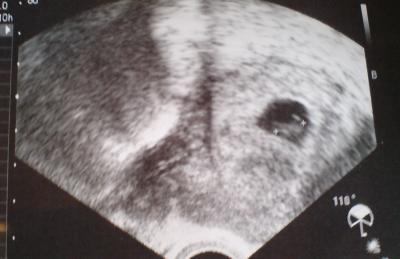

Hier ist mein erstes Bauchbild gemacht bei 7+1

Bild zu Mein 1. Bauchbild - Forum für März - Mamis

Süüüüß, schön wie sich Dein Zwergl eingekuschelt hat

Ein schönes Ultraschallfoto hast du da... LG Tina

Bauchbild????? Aber schön das US-Bildchen.....